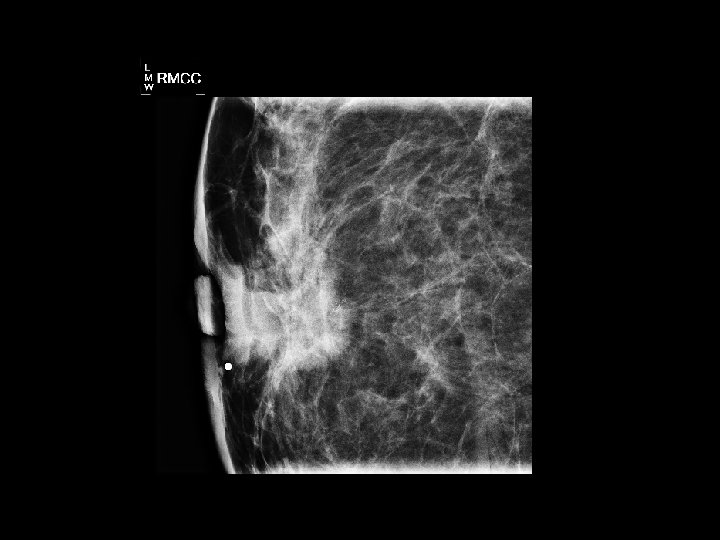

Image Samples

First post-contrast subtraction